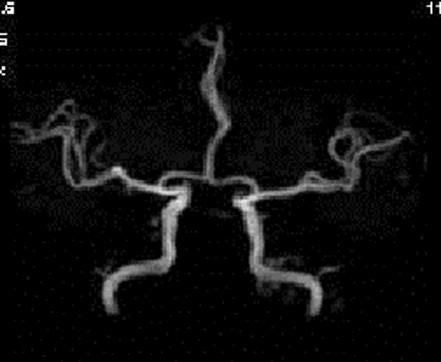

又、脳の萎縮等、認知症の診断にも役立ちます。 - 頭部MRA(MRIを用いた脳血管撮影)

- くも膜下出血の原因である脳動脈瘤や動静脈奇形などが見つかります。

又、血管の閉塞や狭窄等脳梗塞の発症リスクを診断することが可能です。 - 頚部MRA(MRIによる頚部血管撮影)